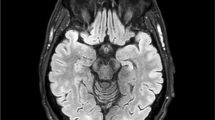

Surgical approach (Fig. 1)

a A schematic visualisation of the optic tract based on Ebeling et al.[7] and Yamamoto et al. [40] The yellow dashed ovals represent areas at risk after trans-sylvian or temporobasal approach. While the trans-sylvian approach would mostly damage the Meyer’s loop, the damage inflicted by the temporobasal approach is more mesial and posterior and could affect the optic radiation bundle. b Trans-sylvian approach and c temporobasal approaches present the optic radiation (yellow), delineated in two different patients before surgery. After image fusion, the optic radiation has been transferred to the postoperative MRIs (coronal T2 images). The purple points on the axial images and their corresponding localisation on the coronal T2 images show the areas, where the optic radiation has been compromised by the resection cavity. CGL corpus geniculate laterale